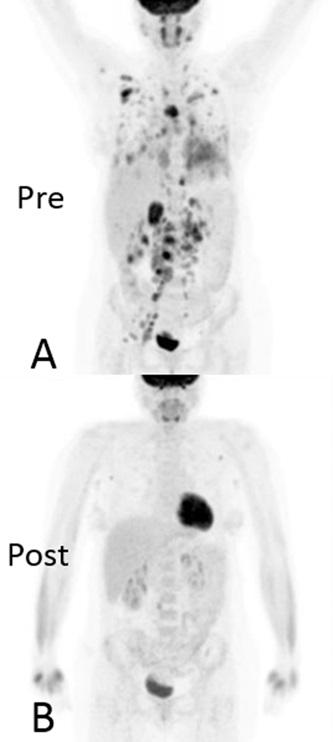

In this proof of concept study, Dr Stephen Jolles and colleagues from the University Hospital of Wales used an imaging technique called FDG PET-CT to simultaneously assess anatomical structure and metabolic activity in a patient with GLILD. FDG PET-CT imaging allows the detailed anatomical structure obtained by a CT scan to be overlaid and combined with PET images of rates of labelled glucose uptake into cells within the tissues; the clinical utility of which has already been proven in oncological imaging. However, FDG PET-CT's use to assess inflammatory disease is an emerging field and this paper is the first time that this technique has been employed to assess both anatomical and metabolic extent of the disease and to assess treatment response in the setting of GLILD.

The images (supplied) show that FDG PET-CT provides new insights into GLILD, showing widespread, high levels of metabolic activity not restricted to the lungs but affecting lymph nodes (even when these are normal in size) throughout the body before treatment. After treatment, clear improvements in both anatomical and functional activity can be observed. The combined FDG PET-CT demonstrates that GLILD is only the pulmonary facet of a highly metabolically active multisystem disease. The very high levels of metabolic activity may have implications for the development of autoimmunity and malignancy, both of which occur at higher frequency in patients with GLILD.

This study is the first time that the imaging technique, FDG PET-CT, has been used to assess the combined lung structure and metabolic activity in a patient with GLILD before and after treatment. The images are striking and enlightening in that they reveal the highly metabolically active multi-systemic nature of the disease. It remains to me amazing the ability of this technique to overlay structure with metabolic functional activity in this way."